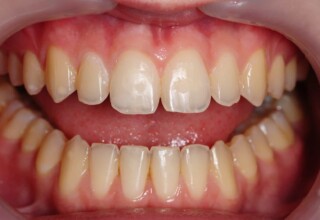

Δυσχρωμικοί άνω πλάγιοι τομείς

Αρχική εμφάνιση

Τελική εμφάνιση